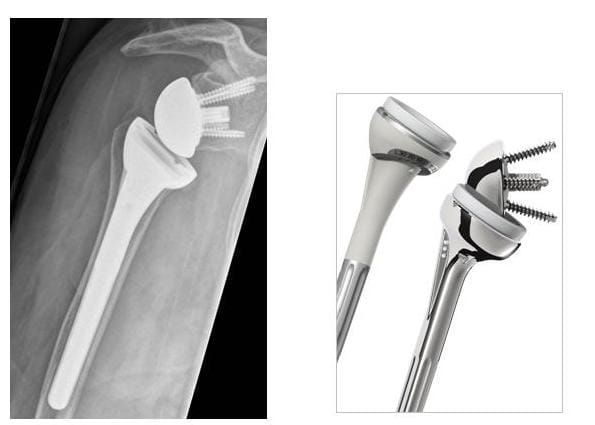

Mit dieser Prothese werden standartmäßig fortgeschrittene Arthrosen der Schulter behandelt. Die Schaftverankerung kann auch bei schlechterer Knochenqualität zementiert erfolgen. Der Prothesenkopf kann 3-dimensional an den Schaft angepasst werden, wodurch eine optimale Wiederherstellung der Anatomie möglich ist. Die Gelenkpfanne kann ebenfalls ersetzt werden. Man spricht dann von einer Schultertotalprothese.

Röntgenbild anatomische Schulterprothese

Röntgenbild einer Schultertotalprothese (Orthopädie, Klinikum Bielefeld)

Prothesenmodell (Fa. Depuy)